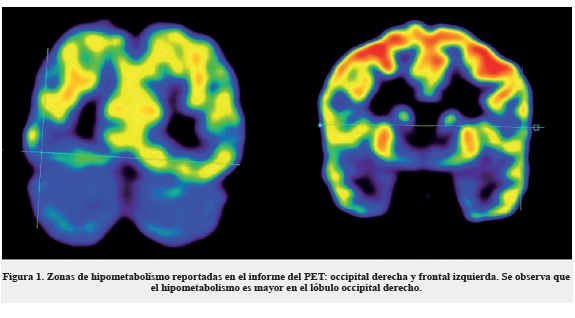

Los estudios de resonancia magnética estructural han sido negativos en la detección de posibles lesiones. El estudio de PET-CT indica disminución del metabolismo en la región occipital derecha y la región frontal izquierda sin que haya alteraciones morfológicas asociadas. La Figura 1 muestra la disminución del metabolismo en la zona occipital derecha. El videomonitoreo electroencefalográfico (VEEG) es anormal por la presencia de una zona epileptogénica estimada en el cuadrante posterior del hemisferio derecho (Tabla 1 y Figura 2).